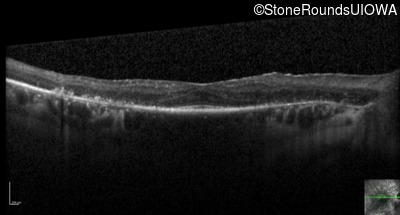

Optical Coherence Tomography - Right - 20/50 +1

Exemplar / OCT Stack

Optical Coherence Tomography - Left - 20/25 -1